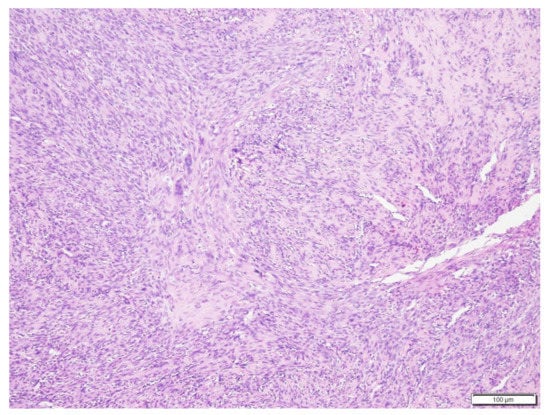

Successful Treatment of Vertebral Osteosarcoma in a Cat Using Marginal Surgical Excision and Chemotherapy

2. Materials and Methods

3. Results